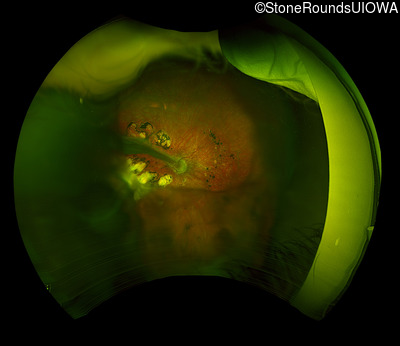

Case Level Images